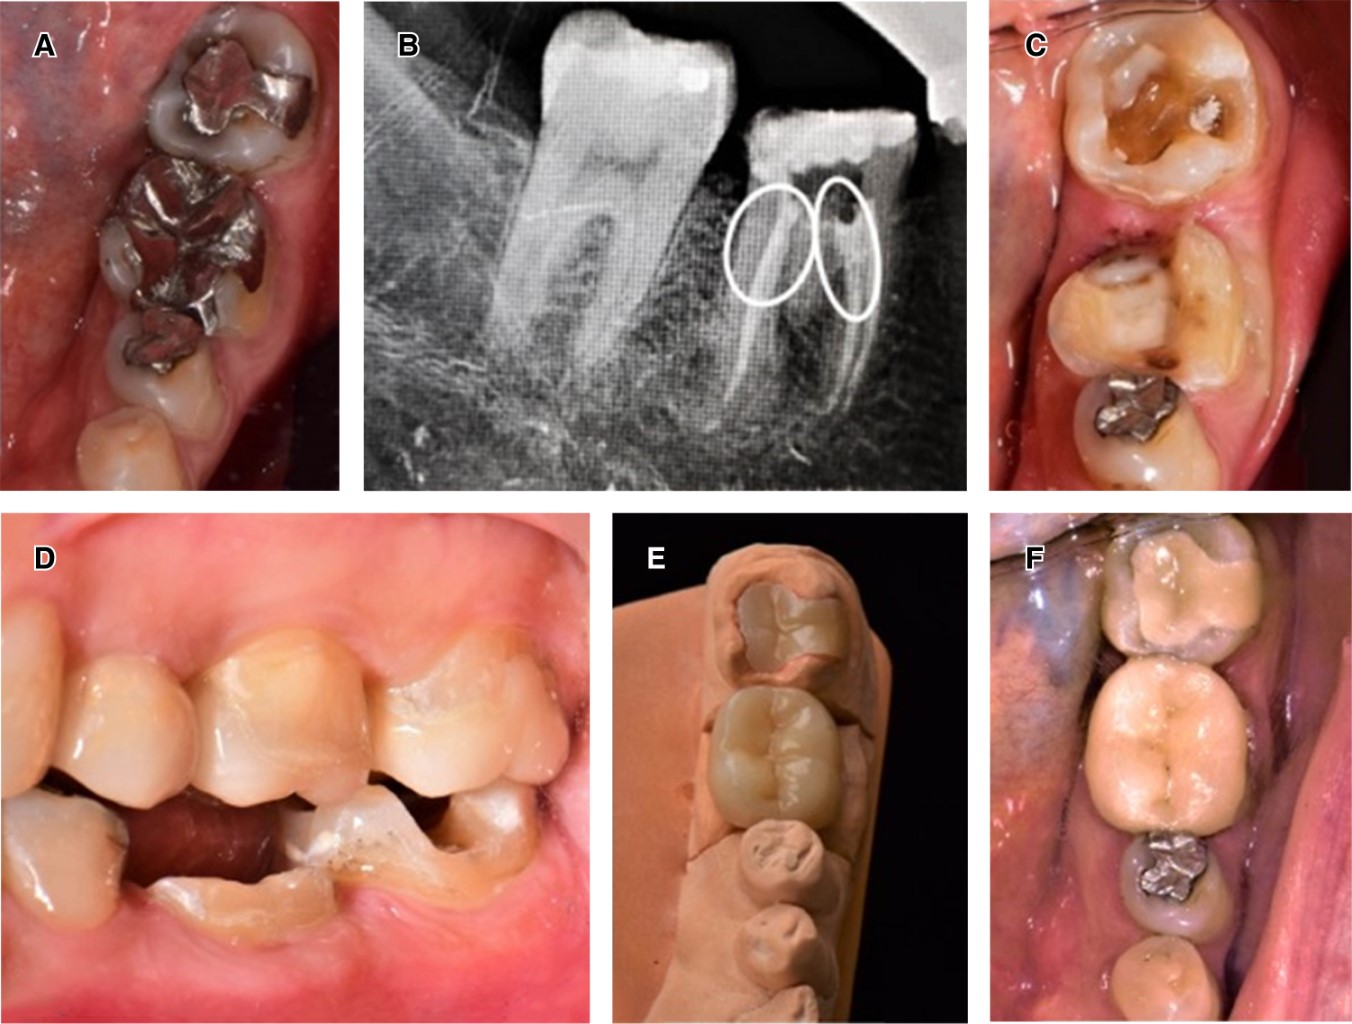

CASO 1

Mujer de 46 años de edad que acude a la Clínica de Odontología Restauradora Avanzada en el Postgrado de Odontología de la Facultad de Odontología de la UNAM, con el motivo de consulta de restaurar los dientes 36 y 37 (Figura 1A), despulpados, con restauraciones provisionales, lesiones de caries recidivante y espacio interoclusal disminuido en relación con sus antagonistas, tejido remanente coronario limitado en ambos dientes, pero en especial en el diente 36 y con un mínimo grosor a nivel de la furca, se indica su extracción para posterior colocación de implante. En el análisis del diente 37, éste contaba con altura de 4 mm y un grosor de 3 mm en todas sus paredes, por lo cual se determina la realización de una endocorona (Figura 1B).

Con aislamiento absoluto, se procede a la preparación del espacio de la cámara pulpar, para crear divergencia oclusal entre 5 y 8 grados, descontaminación con hipoclorito de sodio al 5% y compensación de socavados con resina fotocurable FiltekTM Z350 (3M-ESPE) brindando paredes rectas y lograr la divergencia mencionada, se sellaron los accesos de conductos con cemento polimérico RelyXTM U200 (3M-ESPE), se procedió a tomar impresión con polivinil siloxano (PVS), Elite HD+ (Zhermack) (Figura 1C) y se realiza la obturación temporaria con Systemp onlay (Ivoclar Vivadent). El material restaurativo de elección fue cerómero SR Nexco (Ivoclar Vivadent) por sus características en general y en especial por su resiliencia, resistencia a la fractura y bajo costo (Figura 1D).

En la segunda cita se retira el restaurador temporario, se coloca el aislamiento absoluto, limpieza de la cavidad con clorhexidina en pasta al 2% ConsepsisTM Scrub (Ultradent), se comprueba la adaptación y la altura oclusal de la restauración y se procede a la cementación con RelyXTM U200 (3M-ESPE), se procede a la remoción de excedentes después de un prepolimerizado de 3 segundos, se retira el aislamiento absoluto, se comprueba la oclusión con papel articular de 12 μm, se realizó el pulido con gomas y pasta de pulido para resinas (Figura 1E-F).

Figura 1